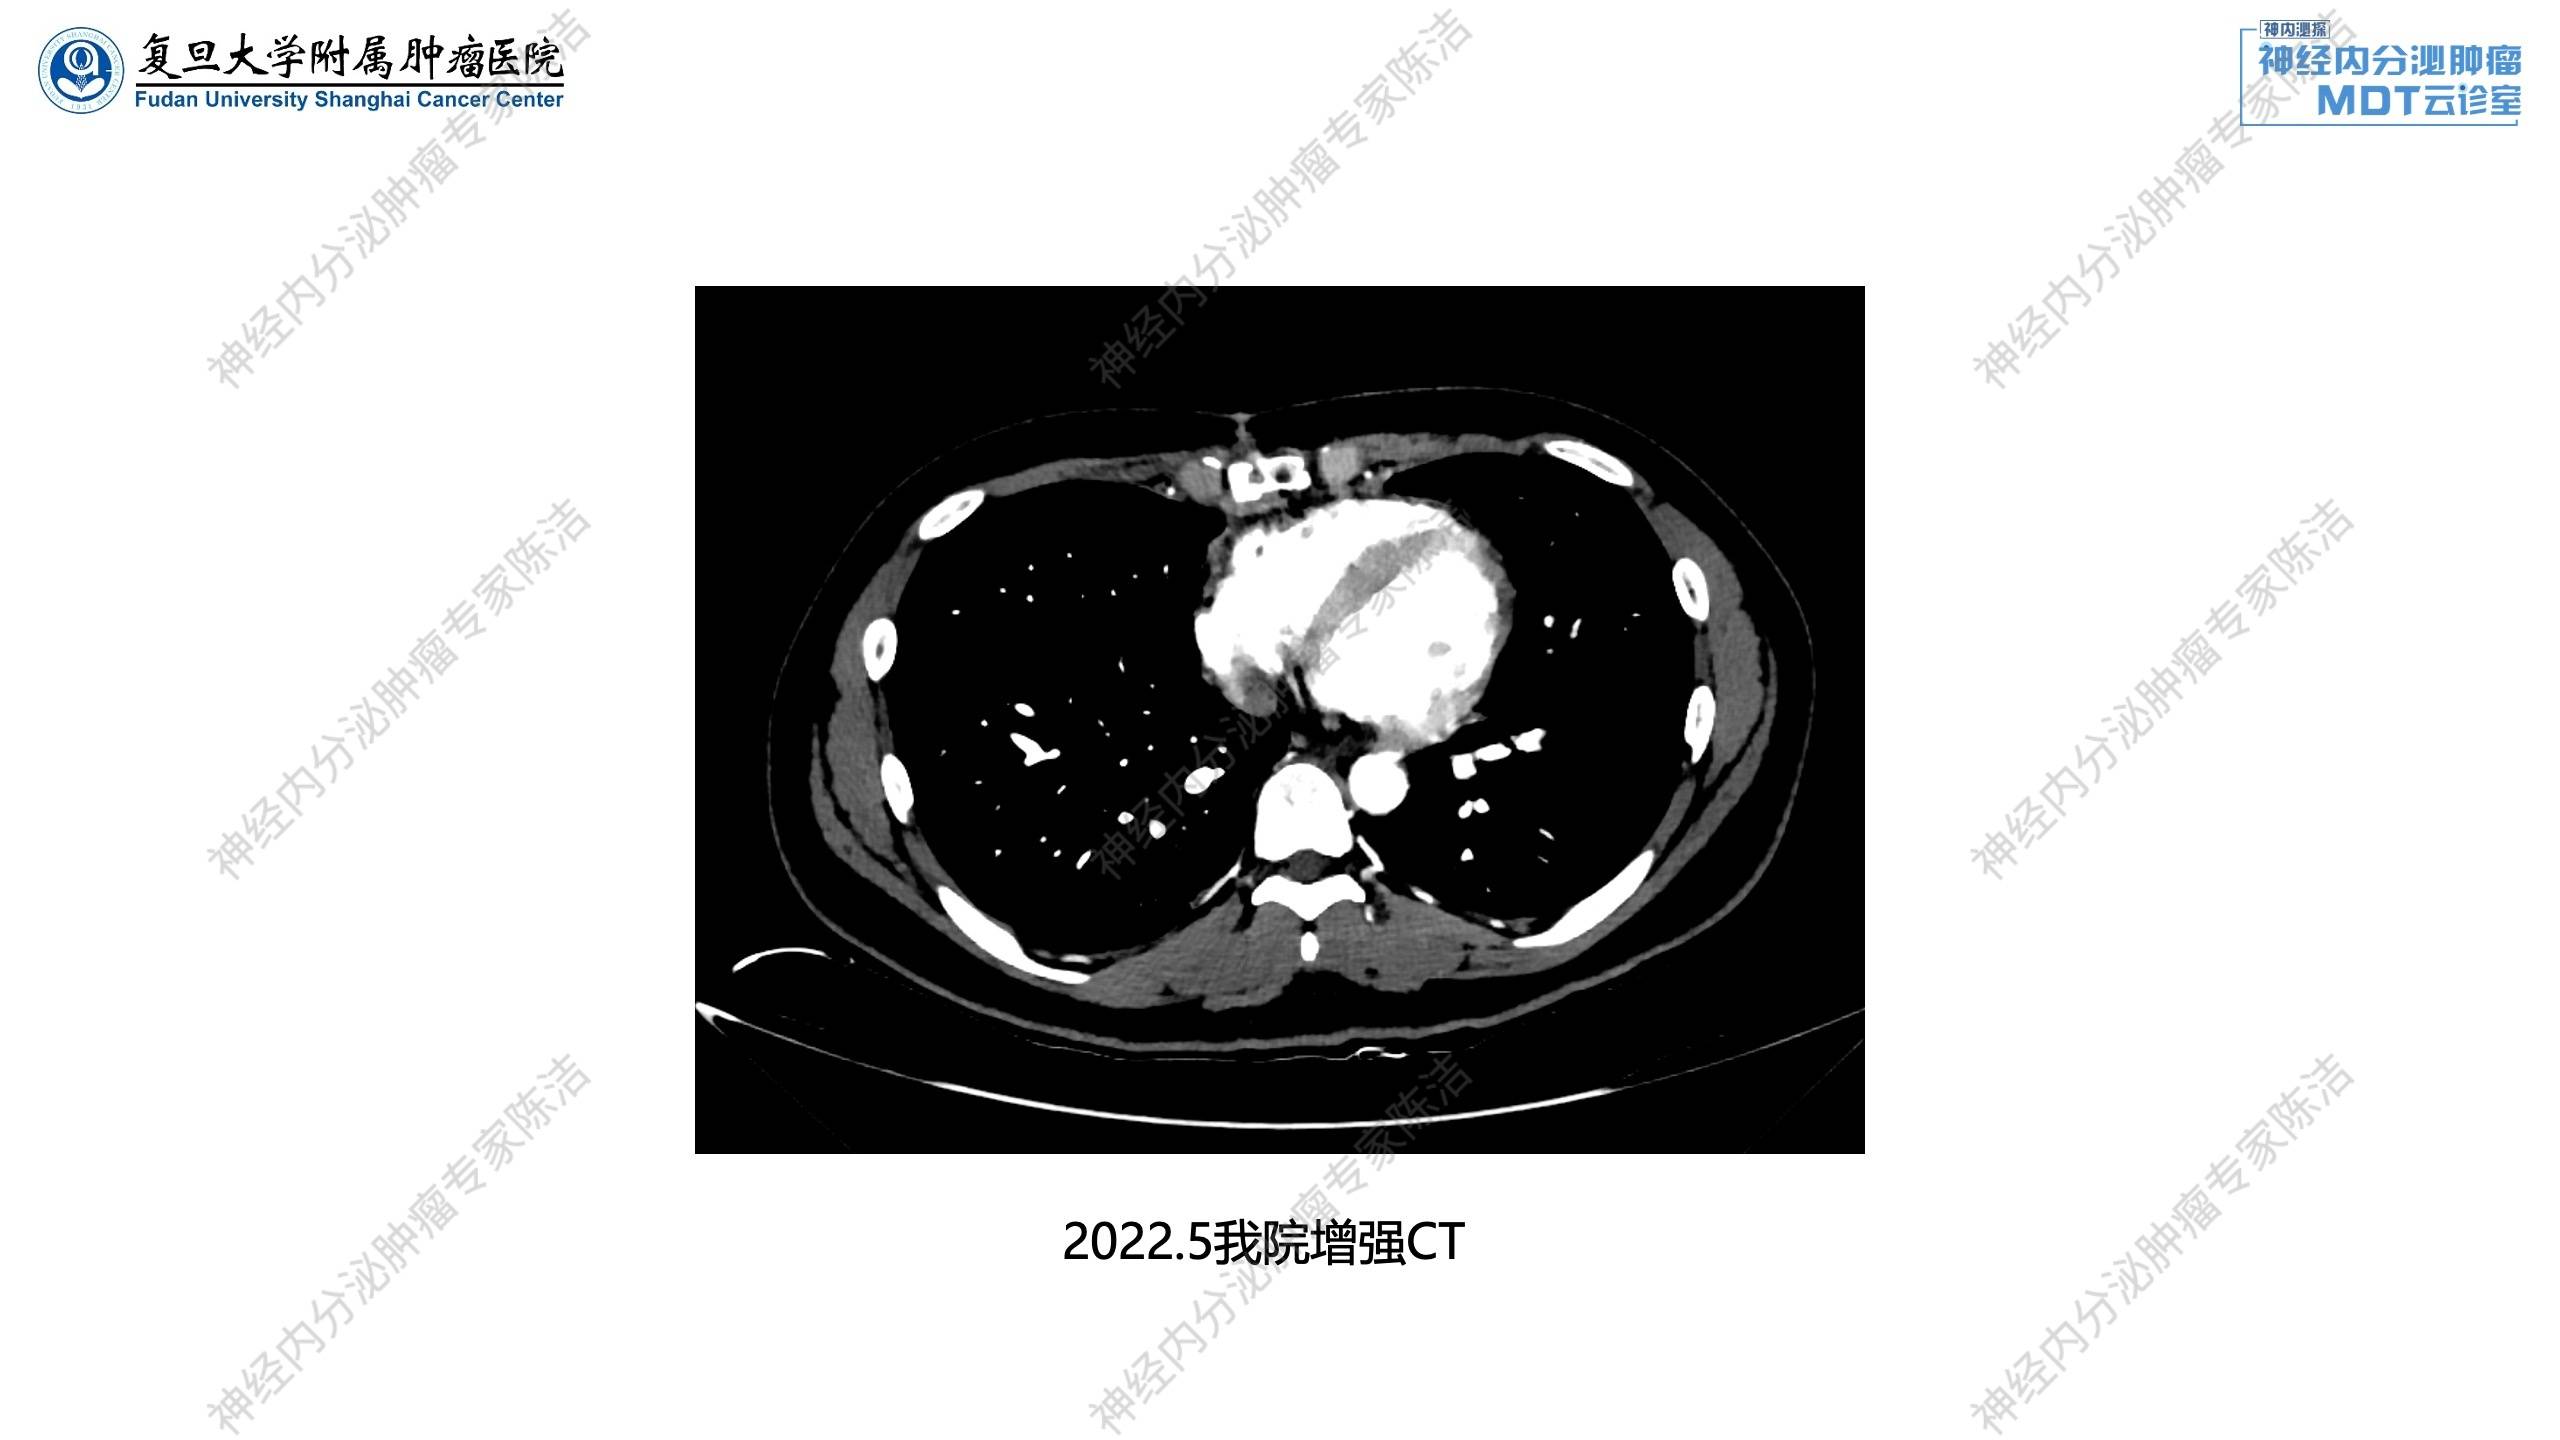

我院诊疗经过

2022年5月:68Ga-SSA-PET/CT提示胸腺不典型类癌术后,局部未见NOC摄取异常增高灶;胰腺体尾部小灶性NOC摄取增高。甲状腺右叶后方结节影,未见NOC摄取增高。

血PTH: 7.000pmol/L, Ca: 2.68mmol/l。腹部CT提示胰腺多发富血供小结节,NET待排。

核医学科徐俊彦教授:该患者术前18F-FDG-PET/CT显示前上纵隔分叶状肿块,FDG代谢轻度增高。术后68Ga-SSA-PET/CT扫描,提示纵隔肿瘤已切除,但在胰体尾发现了小灶性的SSTR高表达病灶,提示胰腺神经内分泌瘤。甲状腺右叶后方存在微小软组织结节(<5mm),MIBI显像没有明显浓聚。这可能是因为病灶太小,且患者PTH和血钙仅轻度升高,功能不活跃,导致MIBI灵敏度不高。

放射诊断科汤伟教授:在胰腺增强CT上,因为病灶都比较小,在几个层面看到胰腺里面有一些小的点状强化,考虑微小pNET的改变。